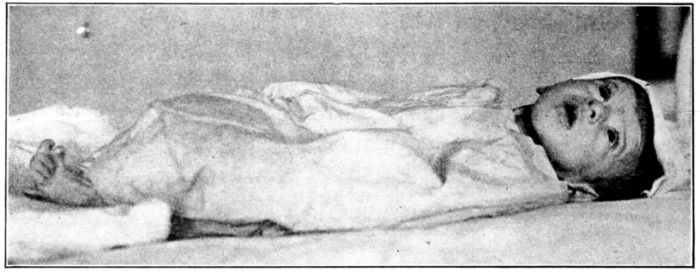

| 140. | Baby partially blind as a result of a faulty diet | 378 |

| 141. | Rachitic and normal babies of the same age | 381 |